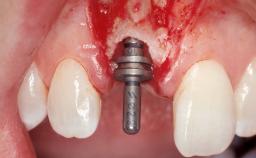

A 42-year-old female patient was referred to our clinic at the School of Dentistry of the University of São Paulo in November 2004, presenting a deficient restoration in the upper left central incisor. The clinical examination revealed no gingival retraction or any signs of gingival inflammation and, therefore, previous periodontal treatment was not considered. The patient presented a high lip line at full smile and a thin tissue biotype. This combination characterized a high-risk situation from an anatomic point of view, which required careful preoperative planning and cautious surgical execution.

Placement Protocol Immediate implant placement

Tooth Site Maxillary incisor or canine

Socket Morphology Single-root socket

Socket Integrity Sufficient, with intact bone walls